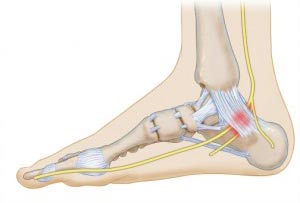

سندرم تونل تارسال

گاهی اعصاب مچ و کف پا ممکن است تحت فشار قرار بگیرند به این وضعیت سندرم تونل تارسال گفته میشود. سندرم تونل تارسال میتواند موجب بروز درد در سراسر پاشنه و مچ پا شود. این عارضه در اثر نامناسب بودن پرونشین (چرخش مچ پا با داخل) یا التهاب تاندون به وجود میآید.